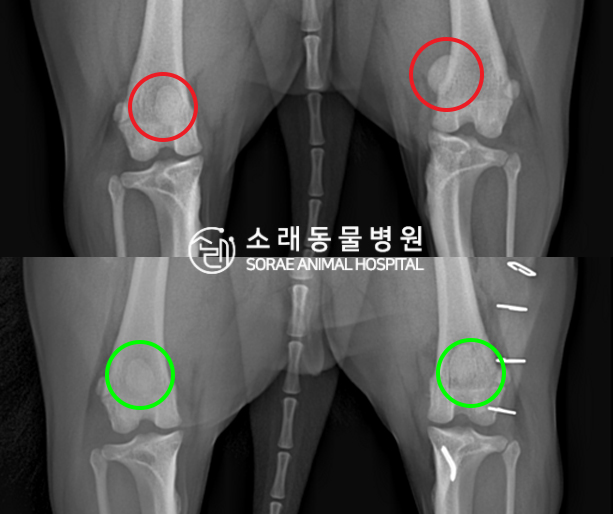

수술전과 수술후에 촬영한 쫑이의 슬개골

방사선 사진입니다. 나란히 놓고 비교해보니

슬개골의 위치에 확연한 차이가 있는 것을

확인해 볼 수 있는데요. 내측으로 탈구되어 있던

슬개골이 원래 제자리인 활차구에 예쁘게

자리 잡고 있는 모습을 확인할 수 있었습니다.